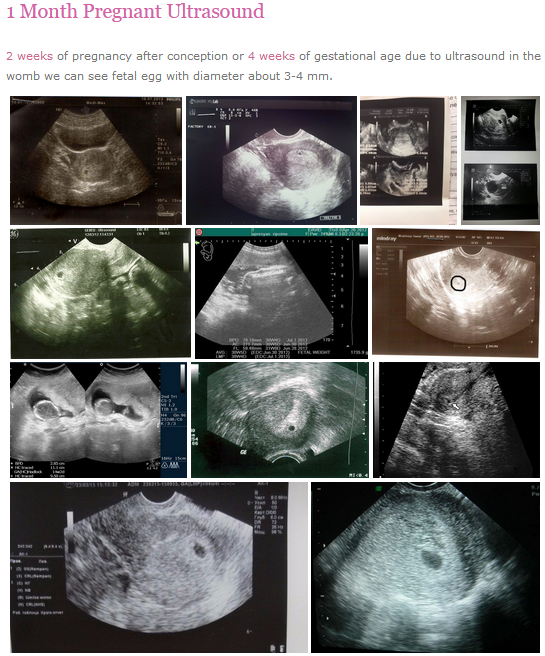

Normal 28 week pregnancy and baby ultrasound, your complete guide.

Normal 28 week pregnancy and baby ultrasound, your complete guide.

Normal 28 week pregnancy and baby ultrasound, your complete guide.

Normal 28 week pregnancy and baby ultrasound, your complete guide …

Normal 28 week pregnancy and baby ultrasound, your complete guide.

Normal 28 week pregnancy and baby ultrasound, your complete guide …

Normal 28 week pregnancy and baby ultrasound, your complete guide.

Normal 28 week pregnancy and baby ultrasound, your complete guide …

Normal 28 week gestation ultrasound in the context of a MVA | Image …